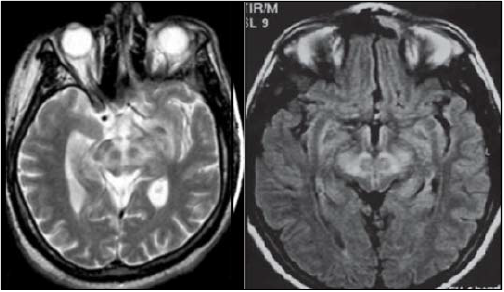

As imagens são tomografias computadorizadas no plano axial, em T2 e flair, com um achado característico que chama

a atenção; analise-as.

Qual a patologia mais comumente relacionada ao achado nas imagens anteriores?